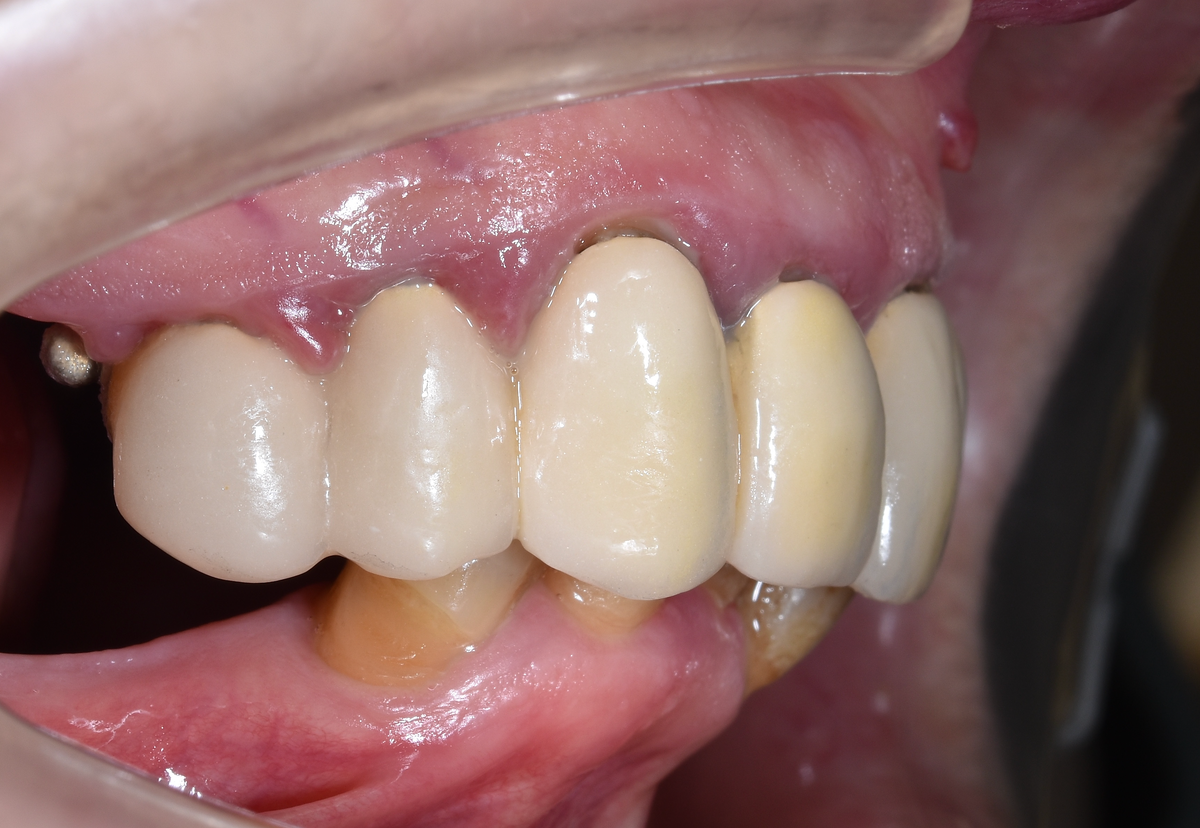

Операцию разбили на два этапа в один день. Начало в 12:00, первый этап завершён к 14:00. Сразу установили предвременный протез FP1 - без розового пластика, только для формирования контура десны.

Предвременный протез FP1 устанавливается сразу после операции. Его задача - даже не эстетика и уж точно не полноценное жевание, а формирование правильного контура десны. Ткани формируются под протезом, принимая нужную форму сразу.

Этот протез изготавливается ещё до операции. А благодаря новому интраоральному сканеру мы можем сразу же прикрутить его - быстро, потому что экономим время на этапе снятия слепков для настоящего временного протеза, который изготавливется после операции, который крепок достаточно, чтобы можно было жевать после приживления имплантатов. Таким образом, сейчас пациент не выходит из клиники без зубов - даже на один день.

Через несколько дней, когда изготовится полноценный временный протез, а десна сформируется, поменяем хлипкий на адекватный и отпустим человека домой. С нормальным постоянном пациентка будет жить несколько месяцев, пока имплантаты окончательно не интегрируются с костью.

Кровь - раны свежие:

А протез предвременный.

-8